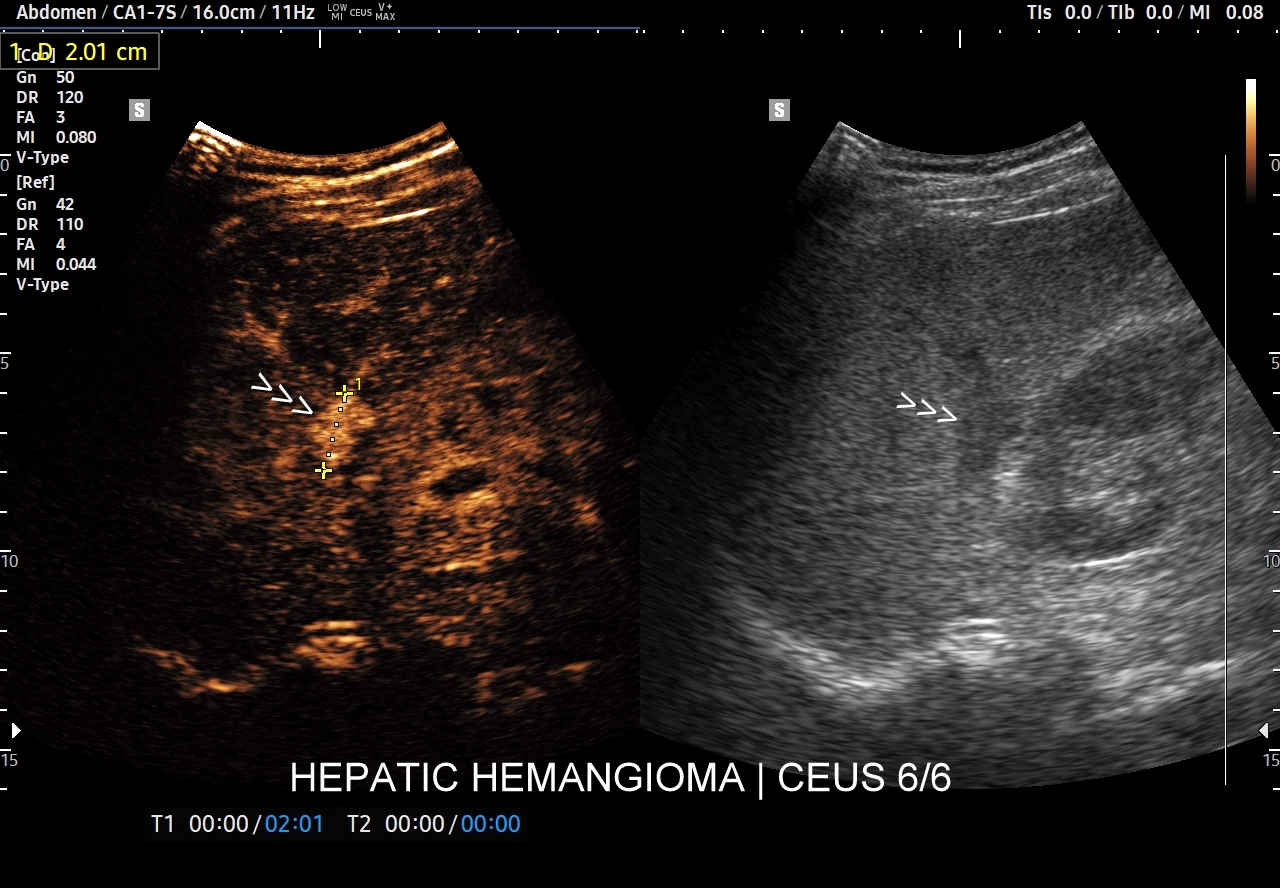

Najbardziej charakterystyczną cechą naczyniaka wątroby w badaniu CEUS jest jego wypełnianie w postaci guzkowej (ang. peripheral nodular enhancement) od obwodu ku centrum zmiany (ang. centripetal). Szybkość wypełniania bywa różnorodna, może być powolna lub szybka. W przypadku szybkiego wypełniania (tzw. flash-filling), w celu wykazania charakterystycznego centrypetalnego wypełniania niezbędna może być postprocessing’owa analiza poklatkowa zapisanego nagrania badania. W fazie późnej naczyniak wątroby pozostaje izowzmocniony lub hyperwzmocniony w stosunku do natywnego miąższu wątroby.

W przypadku dużych naczyniaków obszary, które uległy wykrzepianiu pozostają awaskularne przez wszystkie fazy badania CEUS, tj. nie wypełniają się kontrastem (nonenhancing). W przeciwieństwie do powyższego konstelacja, w której to w fazie wczesnej pojawia się wzmocnienie, a następnie w fazie wrotnej lub późnej ulega wypłukaniu (hypoenhancement) świadczy o cechach złośliwych diagnozowanej zmiany ogniskowej w wątrobie i wyklucza rozpoznanie naczyniaka.

W razie braku pewności co do wypełnienia guzka w stosunku do natywnego miąższu wątroby, tj. słabo dostrzegalnych wizualnie różnic, pomocne może być wykorzystanie w ramach obróbki postprocessing’owej ilościowej oceny wypełnienia kontrastem poszczególnych obszarów, tj. guzka i prawidłowego miąższu, w ramach analizy TIC (ang. time intensity curve). Metoda ta polega na umieszczeniu jednego znacznika w zmianie ogniskowej, drugiego w kolejnym obszarze, a następnie porównania ich obu pod kątem intensywności sygnału na osi czasu.